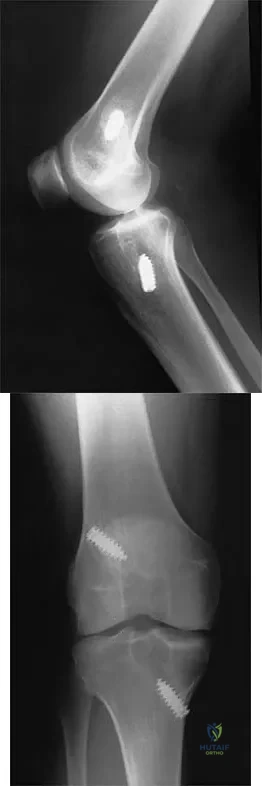

Question 70

A 24-year-old runner who underwent an allograft reconstruction of the anterior cruciate ligament (ACL) 3 years ago now reports anterior knee pain. Examination reveals no swelling or effusion, and the patient has full motion. A Lachman test and a pivot-shift test are negative. Palpation reveals tenderness on the patellar tendon and at the inferior pole of the patella. AP and lateral radiographs are shown in Figures 41a and 41b. Management should consist of